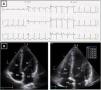

Resting electrocardiogram (ECG) (top) and transthoracic echocardiogram (TTE) (bottom), before detraining. (A) ECG with voltage criteria for LV hypertrophy and marked deep T-wave inversion in leads I, II, III, aVF and V3-V6, with ST-segment depression; (B) TTE (apical 4-chamber view), showing moderate asymmetric hypertrophy, localized at the mid-apical segments of the left ventricle, with maximum wall thickness of 16 mm. LA: left atrium; LV: left ventricle; RA: right atrium; RV: right ventricle.

Case reportA 22-year-old Caucasian male soccer player undergoing a pre-participation exam (PPE) presented a very unsettling ECG (Figure 1), highly suggestive of cardiomyopathy. He was asymptomatic, had a normal physical exam and his family history was negative for cardiovascular (CV) disease and SCD. He had been playing amateur soccer at regional level for ten years, training three days a week (90 min), with a weekly match. The transthoracic echocardiogram (TTE) revealed a nondilated left ventricle with asymmetrical apical hypertrophy (maximum LV wall thickness 16 mm) (Figure 1 and Video 1) and normal left ventricular ejection fraction and diastolic function. On cardiac magnetic resonance (CMR) the maximum apical thickness was 14 mm and the LV cavity had a spade-like appearance during diastole. No late gadolinium enhancement (LGE) was detected (Figure 2). Holter monitoring and treadmill exercise testing were normal (16 metabolic equivalents, no symptoms and no arrhythmias) and genetic testing was negative for the following mutations: MYH7, MYBPC3, ACTC1, TNNT2, TNNI3, TPM1, MYL2, MYL3, CSRP3 and TCAP.

Follow-up assessment was performed four months later. He had reportedly respected our warning and barely exercised in the meantime. While still abnormal, the ST-segment depression and deeply inverted T waves had become less prominent (Figure 3). We repeated the TTE and had a similar impression: although maximum wall thickness in the apex was significantly decreased (10-11 mm) and not diagnostic of HCM, the TTE seemed clearly abnormal, given the small cavity, the abnormal geometry and the apical gradient (Figures 3 and 4 and Video 2).

Resting electrocardiogram (ECG) (top) and transthoracic echocardiogram (TTE) (bottom), performed four months after detraining. (A) The ECG shows a clear improvement of the T-wave abnormalities in the inferior and lateral leads, although the ECG is still abnormal; (B) on TTE, a decrease in both septal and apical LV wall thickness is evident (maximum 11 mm). LA: left atrium; LV: left ventricle; RA: right atrium; RV: right ventricle.